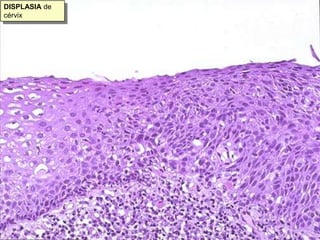

Este documento resume diferentes tipos de necrosis y otros procesos patológicos encontrados en anatomía patológica general. Describe necrosis coagulativa como infartos de miocardio y riñón, necrosis licuefactiva como infartos cerebrales, y otros tipos como necrosis grasa pancreática y necrosis caseosa en tuberculosis pulmonar. También cubre procesos como apoptosis, atrofia, hipertrofia, hiperplasia, metaplasia, displasia, y acumulaciones de sustancias como hemosiderina, amiloide y calcificaciones.